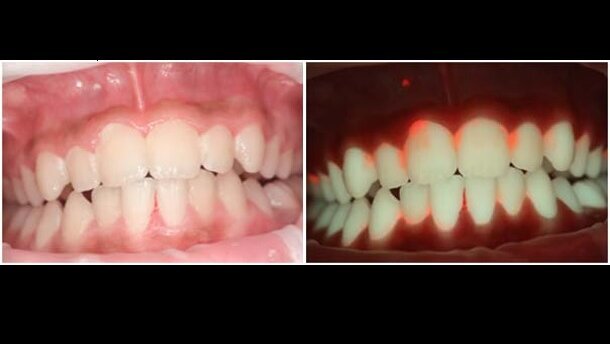

De camera maakt gebruik van Quantitative Light-induced Fluorescence: wanneer tanden met sterk blauw licht wordt aangestraald, sturen zij licht in het groene spectrum terug. Zit er plak op de tanden, dan weerkaatst dit als rood licht. Met verschillende filters vangt de camera het teruggekaatste licht op; hoe sterker het rode licht, hoe meer tandplak. Door eerst een foto van het gebit te maken met normaal (wit) licht en vervolgens met het blauwe licht, kan de camera een foto construeren van het gebit met tandplak en zo het begin van tandbederf aantonen. Zo kunnen tandarts en patiënt direct zien welke delen van het gebit risico lopen om bijvoorbeeld cariës te ontwikkelen. Op basis daarvan kunnen poetsinstructies worden gegeven.